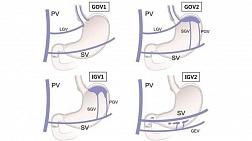

- Классификации